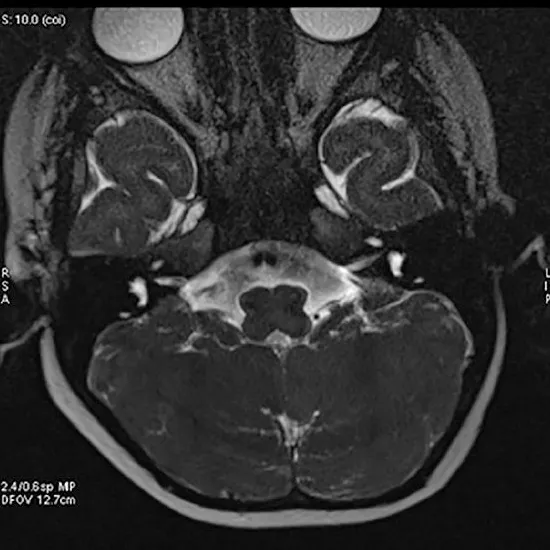

MRI Internal EAR - Test, Procedure & Cost

MRI Internal EAR

MRI internal ear is a non-invasive diagnostic imaging process to check the internal auditory canal of the ear.

This painless non-invasive technique uses strong radio waves and magnetic fields to get precise imaging near the bony canal that conveys the nerves and blood vessels from the lower brain to the inner ear.

MRI Internal Ear is a Magnetic Resonance Imaging non-invasive medical diagnostic tool used to look for abnormalities in the Internal Ear. MRI of the Internal Ear is used to show the tumours, fractures, injuries etc. in the internal ear.